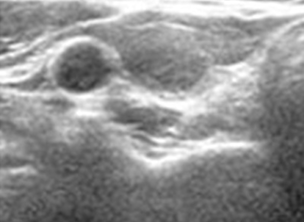

실제 환자의 변화

-

- 치료 전

- 갑상선 낭성 양성 결정

- 1개월 후

- 80% 크기 감소

- 4개월 후

- 95% 크기 감소